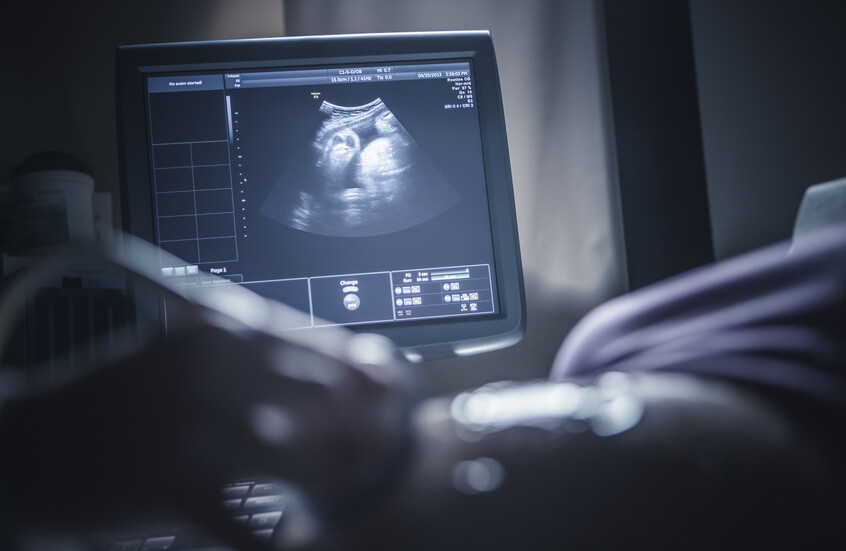

التعرض لمادة كيميائية شائعة أثناء الحمل يخلّ بتطور الجنين!

حذر باحثون من أن تعرض الجنين داخل الرحم حتى لمستويات منخفضة من مادة كيميائية شائعة، يمكن أن يتسبب في اضطراب النمو الطبيعي، مع ظهور تأثيرات تؤدي إلى “تأنيث الذكور وتذكير” الإناث”.

وأشار الباحثون إلى أن تعرض الجنين داخل الرحم حتى لمستويات منخفضة من مادة ثنائي الفينول أ (BPA) الصناعية، قد يؤدي إلى اضطرابات دائمة في النمو الجنيني، مع آثار طويلة المدى على الصحة.